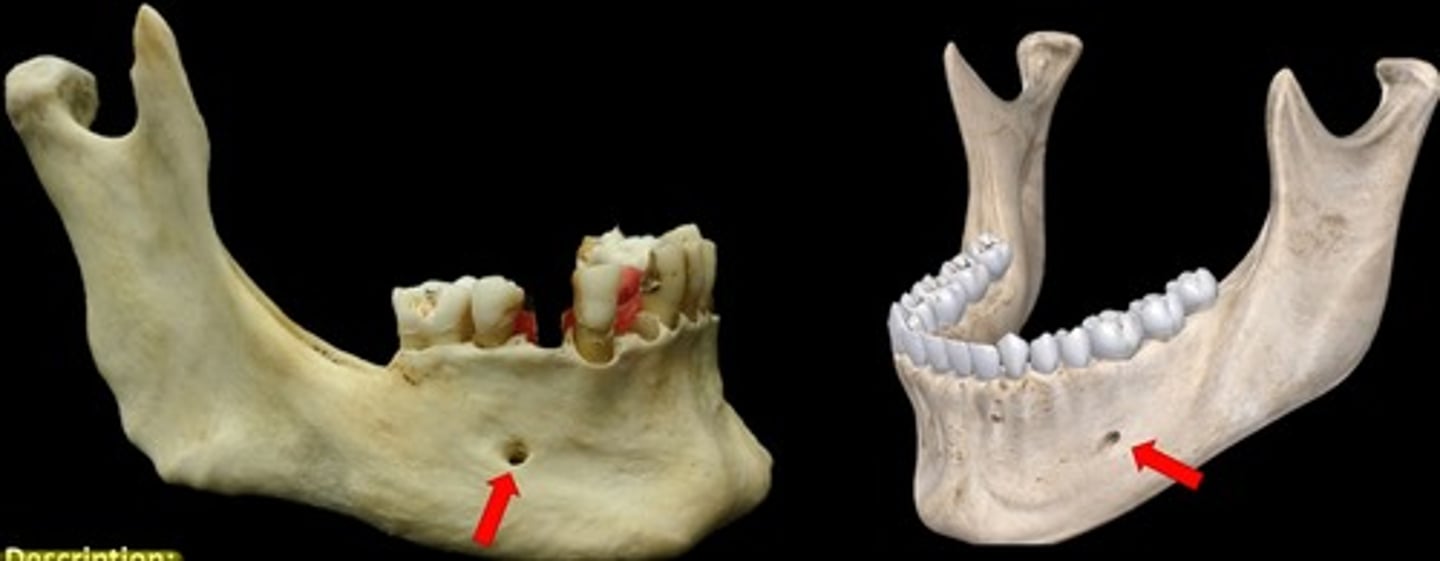

What is the mental foramen?

information on the mental foramen

radiolucent & in the region of the mandibular premolars

What does the mental foramen look like radiographically?

What could the mental foramen be misdiagnosed as?

a periapical lesion (cyst, granuloma, or abcess) because of its apical location

-in some cases